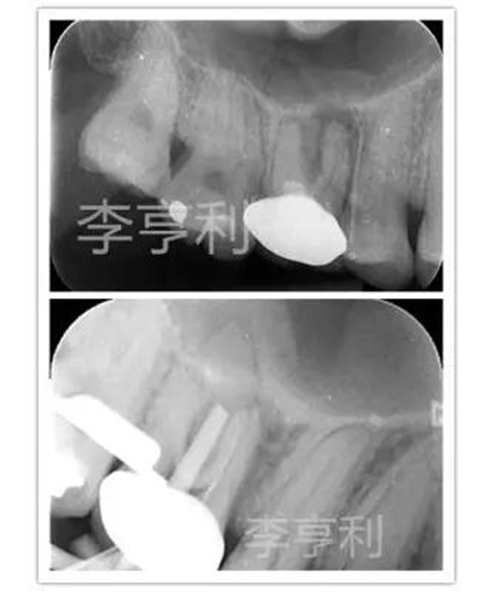

16由于出現(xiàn)瘺管,被轉診醫(yī)生診斷為慢性根尖膿腫并開始根管治療。醫(yī)生只能疏通MB到根尖,其它根管均鈣化不通,故轉至我處 (圖上)。

當重新打開患牙時,P根和DB的冠1/3已經(jīng)被轉診醫(yī)生在探尋根管時大范圍破壞,而且在顯微鏡下仍未能找到根管。隨后告知患者16較差的根管消毒和預后,但患者表示強烈保存患牙的欲望。故決定進行根管治療,但出于對剩余牙體組織的保存,僅預備通暢的MB2和擴大MB的根尖預備,不再嘗試疏通DB和P (圖下)。

術后片顯示除MB根充填能達根尖部,DB和P的根充物都欠充且錐度過大,單純技術要求來看,這是不及格的根管充填 (圖左);

1年回訪發(fā)現(xiàn)16瘺管完全消失,X片也能觀察到明顯的根尖暗影縮小 而且患牙也無任何主觀癥狀,且能正常進行咀嚼,所以從臨床角度來看,這能視為成功的根管治療 (圖右)